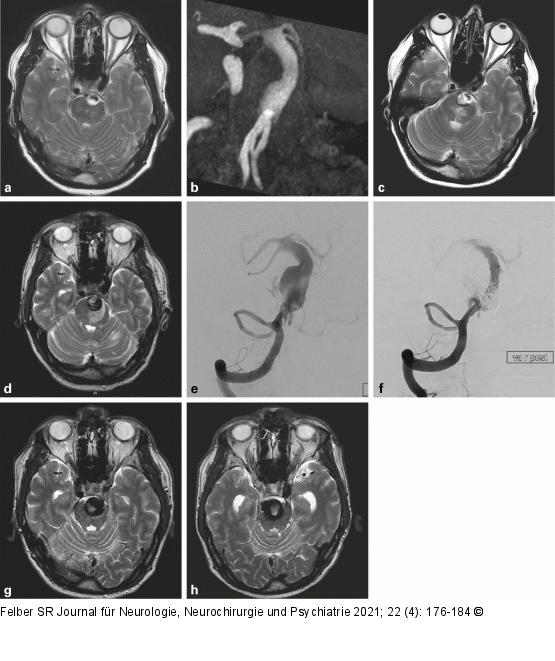

Abbildung 3a-h: Arteriosklerotisches Aneurysma Der 68-jährige Patient erlitt im Mai 2019 eine erstmalige Hirnstammischämie mit reversiblem neurologischem Defizit. Das MRT (a) zeigte ein teilthrombosiertes fusiformes Aneurysma der A. basilaris (b). Im Oktober 2019 erneute Hirnstammischämie mit bleibender Hemiparese, das Aneurysma hatte sich vergrößert, der thrombosierte Anteil hatte zugenommen (c). Bis November 2019 hatte die Hemiparese deutlich zugenommen, das Aneurysma hatte sich weiter vergrößert; es bestand nun ein ausgeprägtes Perifokalödem in der Brücke links (d). Es folgten Stentimplantationen (Leo 5,5 × 70 mm, Balt Germany, Düsseldorf, Deutschland; p64 5 × 24 mm, Phenox, Bochum, Deutschland), teilweise Ausfüllung der Einstromzone des Aneurysmas mit Coils und Verschluss des linken Schenkels der fenestrierten linken Arteria vertebralis in mehreren Sitzungen (e, f). Im Juni 2020 war angiographisch der Einstrom weitgehend unterbunden (f) und die MRT-Kontrolle zeigte das Hirnstammödem rückgebildet (g). Klinisch war der Patient stabil, aber die MRT-Kontrolle zeigte eine weitere Größenzunahme des Aneurysmas (h). |

Abbildung 3a-h: Arteriosklerotisches Aneurysma